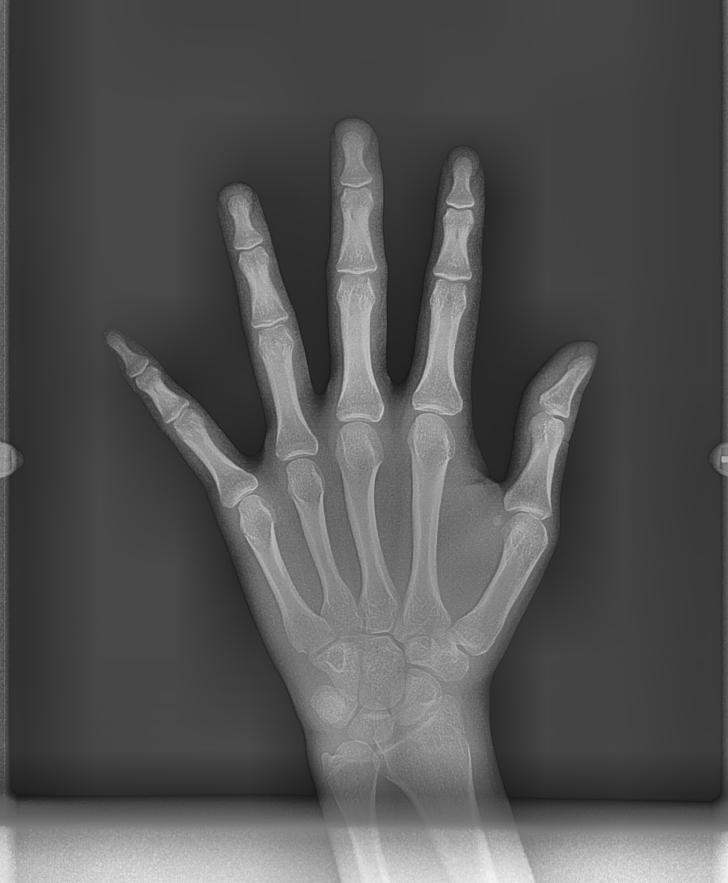

교정 진단을 할 때

성장기 환자분들이 내원하시면

수완부 검사를 추가해서 진행합니다!!

손 사진을 찍으면 성장 단계를 파악할 수 있습니다!

성장이 거의 끝났는지

아직 한참 진행될 예정인지에 따라

치료 계획이 달라지기때문에

찍는 것입니다.